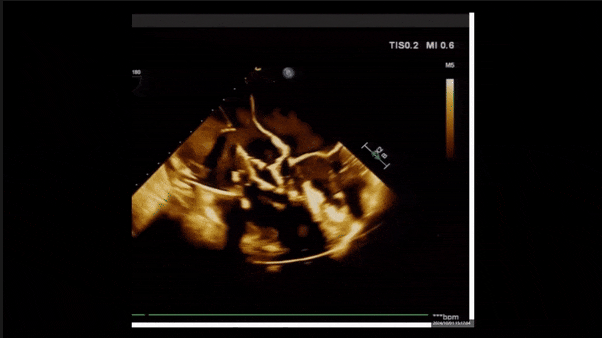

術(shù)后即刻返流

術(shù)后即刻返流三維

術(shù)后三維超聲

術(shù)后即刻經(jīng)食道超聲可見,三尖瓣假體瓣膜位置合適,牛心包瓣葉運(yùn)動狀態(tài)良好,開閉正常,瓣周及瓣葉對合緣處未見明顯返流,心電圖及心包狀態(tài)較術(shù)前無明顯變化。